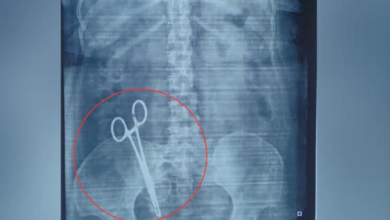

लखनऊ: ऑपरेशन के 17 साल बाद महिला के पेट से निकली कैंची, डॉक्टर पर लापरवाही का आरोप

लखनऊ से एक चौंकाने वाला मामला सामने आया है, जहां एक महिला के पेट में डॉक्टरों द्वारा 17 साल…